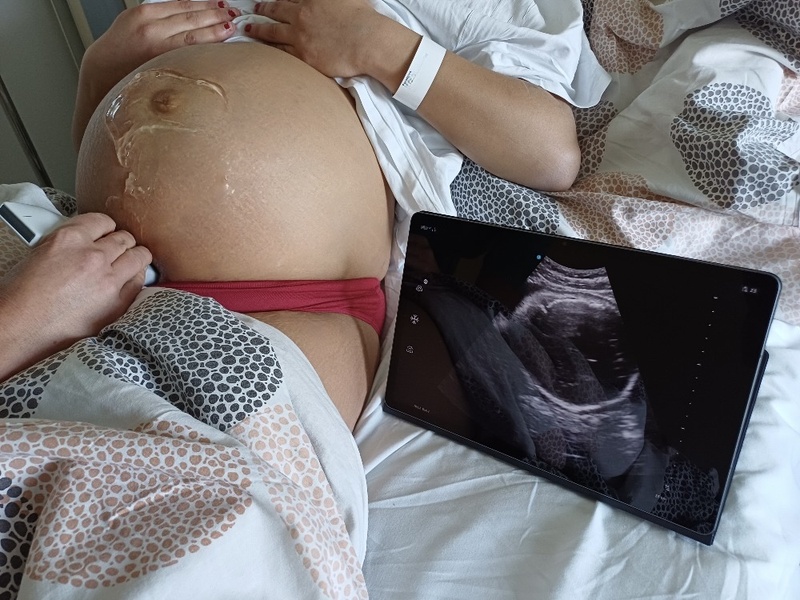

Nemocnice Písek pořídila pro rodičky moderní přenosný ultrazvuk22. května 2024

Nemocnice Písek rozšířila vybavení Gynekologicko-porodnického oddělení o nejmodernější ultrazvukový přístroj s vynikajícím zobrazením. To hraje klíčovou roli při vyšetření nejrůznějších závažných stavů během těhotenství, při porodu i po něm. Nový přístroj je mobilní, takže vyšetření významně urychluje a zároveň zvyšuje pohodlí rodiček.

„Nový ultrazvukový přístroj značky GE Vscan air významné zlepšuje medicínské diagnostické možnosti, zvyšuje bezpečí rodičky i dítěte a zajištuje jim větší komfort. Systém nabízí mimořádné snímky ve vysokém rozlišení a řadu možností jejich ukládání. Jeho součástí je kvalitní bezdrátová oboustranná sonda, kterou lze z každé strany využít pro jiný pohled, a dva tablety. Ty lze v případě potřeby nahradit třeba jen obrazovkou mobilního telefonu. Oproti standardnímu ultrazvuku, který obsahuje set monitoru a obslužného panelu s klávesnicí, včetně napájecích a ultrazvukových kabelů, to vše celé na pojízdném vozíku, je sonda velikosti dlaně zcela jiným přístrojem. Kromě rychlého startování je úžasná také rychlost, s jakou se zdravotníci mohou k rodičce v případě potřeby se zařízením dostat,“ uvedl primář Gynekologicko-porodnického oddělení Nemocnice Písek Michal Turek.

Lékaři písecké nemocnice přístroj používají na oddělení rizikového těhotenství i na oddělení šestinedělí nejen před porodem, ale také po něm. Využívají ho například k vyšetření závažného krvácení po porodu, nebo ke kontrole jizev a břicha po císařském řezu. „Přístroj lze také velmi pružně použít při porodu, kdy je třeba přesně zobrazit uložení hlavičky a hřbetu plodu nebo úhel postupu hlavičky a její vzdálenost od hráze. Lékaři tak vidí, zda je vyšší či menší šance pro spontánní porod, a při případných komplikacích hned zasáhnout,“ řekl Michal Turek.

Vyšetření novým ultrazvukovým přístrojem přináší řadu výhod i rodičkám: za vyšetřením se nemusejí nikam přesouvat, neobtěžují je všudypřítomné ultrazvukové kabely a přístroji nemusí uhýbat ani jejich doprovod, který se jim v danou chvíli věnuje. „Rodičky získají okamžitě důležité informace o svém stavu, který si samy mohou na tabletu i prohlédnout,“ dodal primář.

Ultrazvukové vyšetření je dlouhodobě nedílnou součástí péče o těhotné ženy. Porodnickým pomocníkem číslo jedna je díky své nenáročnosti, šetrnosti vůči matce i dítěti a zároveň vysoké míře získaných informací. V posledních letech se stále více používá k vyšetření ženy na konci porodu. Nový ultrazvukový přístroj je umožňuje rychle a šetrně, bez nutnosti významné změny polohy ženy, například když rodí na porodním gauči – nedávno pořízené a velmi využívané novince písecké nemocnice.